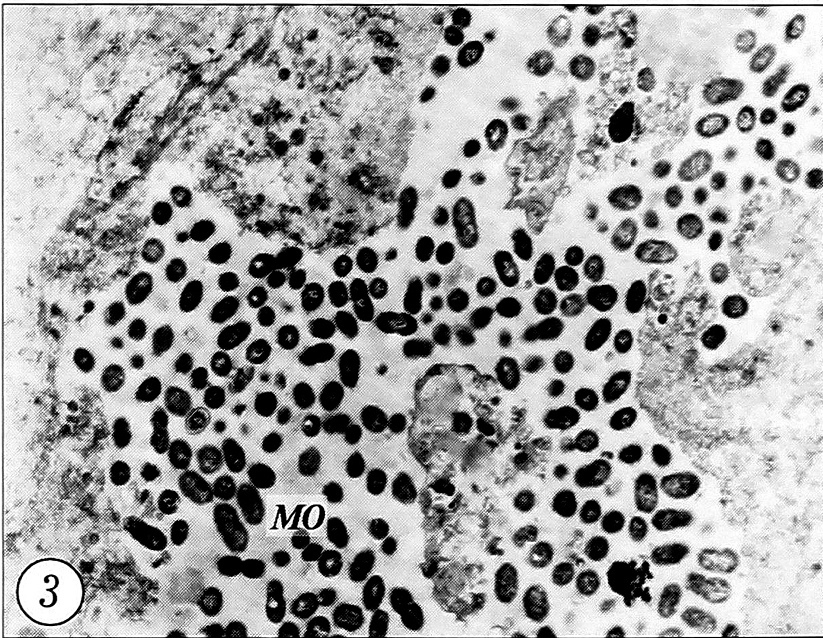

Во 2-й (контрольной) группе животных на 3-и сутки после перелома у поверхности отломков кости определялась выраженная полиморфно-клеточная инфильтрация с доминированием нейтрофильных лейкоцитов и лимфоцитов (рис. 1). Отмечалось появление крупных остеобластов. В мягких тканях, окружающих отломки кости, имелись признаки кровоизлияния. При ТЭМ среди клеток крови, где доминировали эритроциты, на 3-и сутки определялось большое количество микроорганизмов, которые располагались между эритроцитами, не пе-нетрировали их и сами не претерпевали видимых изменений (рис. 2). Максимальное количество микроорганизмов в зоне перелома и окружающих отломки кости мягких тканях определялось на 3-и сутки после перелома. В местах наибольшего скопления микроорганизмов, среди которых различались как палочки, так и кокки, выявлялись многочисленные фрагменты деструктивно-измененных клеток. В этих участках фагоциты (как макро-, так и микрофаги) не обнаруживались (рис. 3).

Рис. 3. Скопления микроорганизмов у поверхности кости и фрагменты распавшихся клеток. 3-и сутки после перелома, контрольная группа (ТЭМ, ув. 7500).